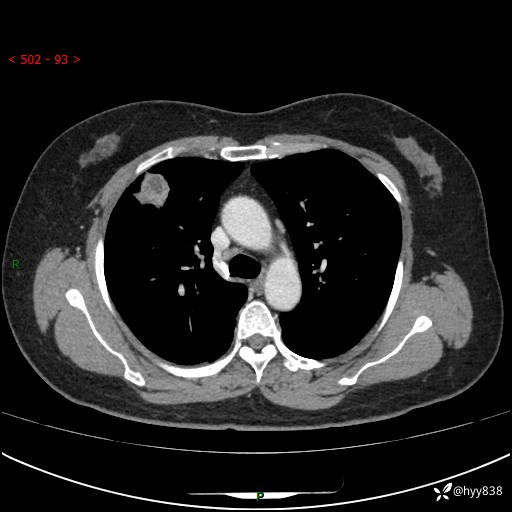

现病史:患者于2天余前无明显出现间断胸痛,无头痛、头晕,无心慌、胸闷、胸痛、呼吸困难、低热、盗汗,无腹痛、腹胀等不适,未进行进一步诊治。于2024.04.14在当地市人民医院行胸部CT检查提示:右肺上叶胸膜下结节。现患者为求进一步诊治,来我院就诊。以“肺肿物”收入我科。 患者自起病以来,精神可,睡眠可,饮食可,大小便正常,体重无明显改变。

胸部CT增强(肺窗,外院平扫)